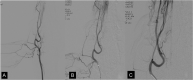

Materials and methods: 2D, 3D, and 4D DSA acquisitions were performed in 5 canines from 3 catheter positions in the common carotid artery yielding 15 2D, 15 3D, and 15 4D datasets. For each territory, 3 vascular segments were chosen for comparison. Images were reviewed by 2 experienced neuroradiologists and were graded by the ability to visualize a segment, its filling direction, and preferred technique. Two visualization modes for 4D DSA were compared (volume-rendering technique and MIP).

Results: 4D DSA was preferred in 73.9% of the image sets; 2D, in 22.7%; and 3D, in 3.4%. 4D DSA MIP rendering yielded superior visualization of very small vessel details; the 4D DSA volume-rendering technique offered superior depth and overlap information and better visualization of the surface details of the vasculature.